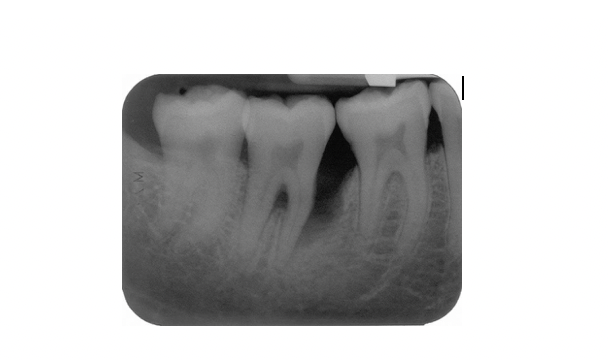

Describe 2 patterns of bone loss evident in this radiograph?

A

• Horizontal and vertical

What explains the development of bone loss on the mesial aspect of the lower right second premolar?

• Presence of plaque accumulation (scalloping) in the distal aspect of the tooth , the canal curvature may have acted as a plaque trap

Following hygiene phase therapy this patient’s oral hygiene was excellent but pockets of >6mm persisted in the lower right quadrant. Open flap debridement was performed

What feature of this patient’s disease which is on the radiograph is most likely to limit the success of this treatment and why?

Fucration involvement due to bone loss making access for cleaning difficult leading to poor prognosis of tooth